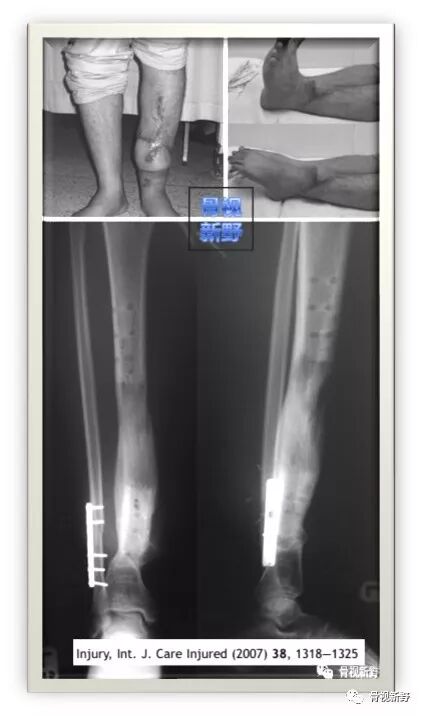

2007年,泰国医生T.Apivatthakakul等人年首次报道了将锁定加压钢板(locking compression plate,LCP)用于胫骨开放性骨折并骨缺损的外固定治疗1例,取得了较好的固定效果。

29岁,男。车祸致左胫腓骨开放骨折,皮肤软组织缺损面积9cm×15cm ,并胫骨节段性骨缺损。急诊清创、胫骨以14孔4.5mm锁定加压钢板(LCP)作外固定(钢板距离皮肤4cm间距)。

● 1周后,皮肤软组织缺损以游离股前外侧肌皮瓣修复。

● 4周后,皮瓣愈合,开始作骨搬移(截骨第7天开始搬运、前3周每天0.5mm;1 mm/天);期间作主、被动关节活动及部分负重。

● 96天后,搬移骨段到达骨端,自体髂骨植骨促进愈合。

● 5个月后,拆除Wagner牵引外架;骨段通过LCP打入1枚螺钉进行稳定。

锁定钢板的外固定应用

LCP继续外固定5月(外固定共10月)后拆除LCP;骨折愈合,踝关节功能良好。